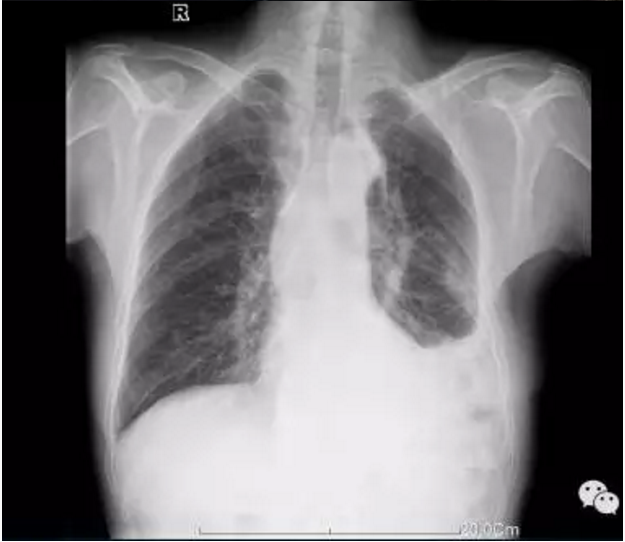

自2017年2月,我院在上级专家老师的指导下,成功为四名癌症患者实施了PICC,之后随着我院派往昆明医科大学第三附属医院学习静脉治疗专科护士的归来,于2017年6月由我院专科护士成功为两名癌症患者实施了PICC,穿刺置管顺利,置管后经胸片显示:导管尖端均在标准位置,患者接受程度良好,标志着我院静脉治疗翻开了全新的一页。